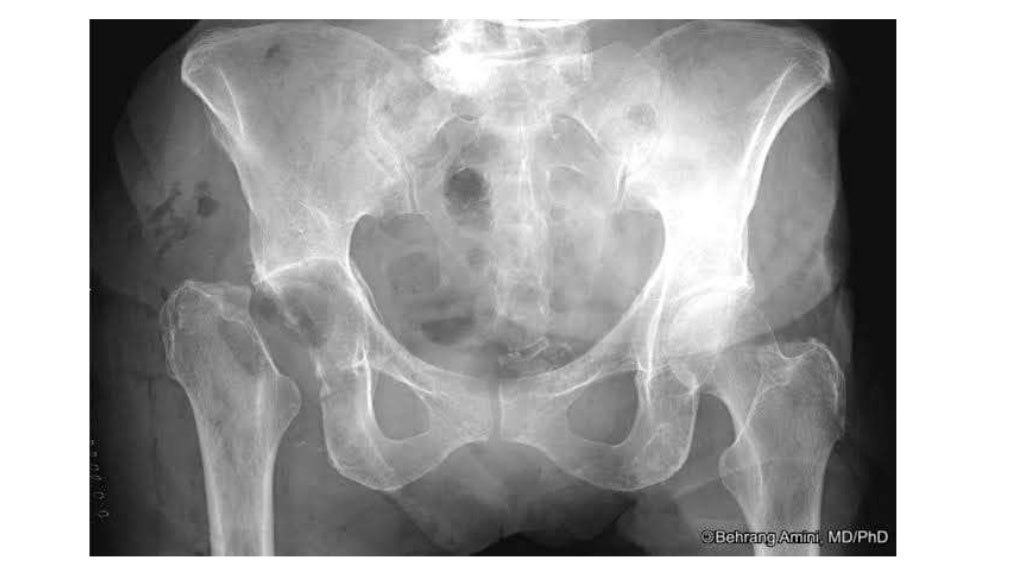

from tbrieder.org